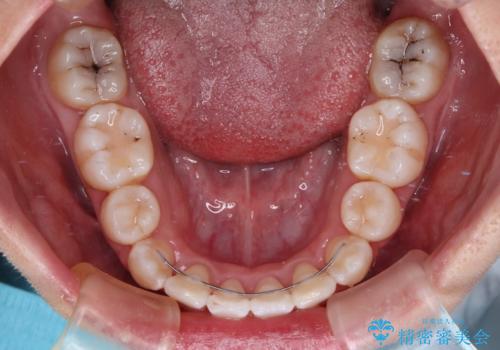

下顎前歯の歯肉が元々薄く、歯肉退縮リスクがあったため、細心の注意を払って治療を進めましたが、残念ながら1歯退縮を起こして歯根が露出してしまいました。

今後、患者様と相談しながら、歯肉移植を行っていく予定です。